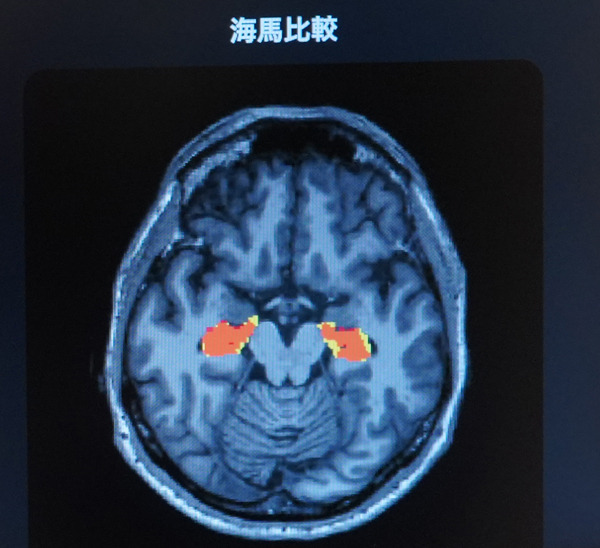

今回開発した技術は、将来の脳の委縮や記憶力に関連するといわれている「海馬」の体積の変化を可視化するもので、可視化された将来の脳の状態を見ることで加齢に伴う脳の変化を見ることができる。

記憶司令塔とも呼ばれている「海馬」に注目すると、海馬が萎縮しているのが解る。萎縮すると「認知機能」に影響が出る可能性が高いと言われているという。ただ、加齢に伴うシミュレーションのため、萎縮を抑える方法を生活に進んでとりいれることで、今後の萎縮を抑えられる機能性もある。例えば有酸素運動を適度におこなうことは海馬の萎縮を抑え、喫煙は海馬の萎縮を進行させてしまう調査結果もあるという。

この課題に対し、YUADの医学博士・精神科医・認知症専門医千葉悠平医師による医学的監修と、Biomyによる協力のもと、脳画像に画像生成技術の一つであるGAN(敵対的生成ネットワーク:本物に似たデータを生成する生成器と、本物のデータかどうかを見分ける判別モデルが、競い合いながら学習することで、高品質なデータを生成する技術)を活用することで、MRIで撮影した脳画像から将来の脳画像を予測する生成AIを開発。脳全体や認知症、記憶力と関連するといわれている海馬の体積が将来どのように変化するかを予測し、画像を生成する。